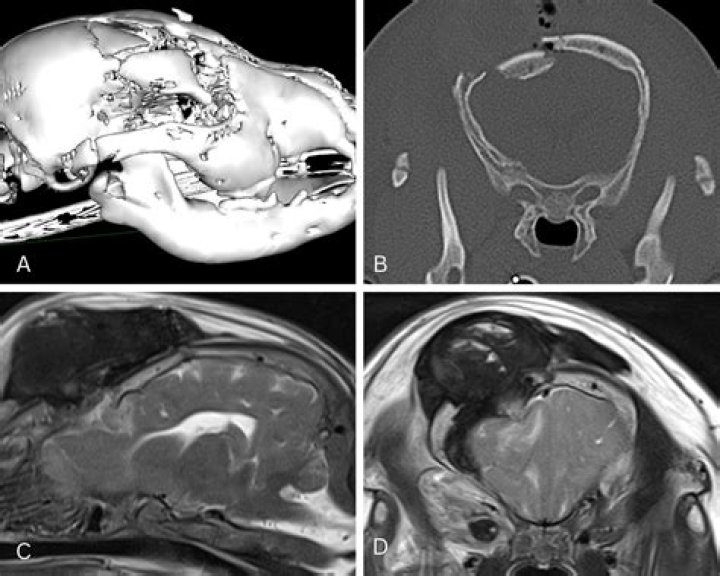

Can a dog survive a skull fracture?

While dogs can survive after a loss of a considerable amount of cerebral tissue, reduction of brain swelling and analysis of damage to stem structure is vital to the prognosis. Brain injury in dogs results from a trauma to the head, leading to neurological dysfunction.